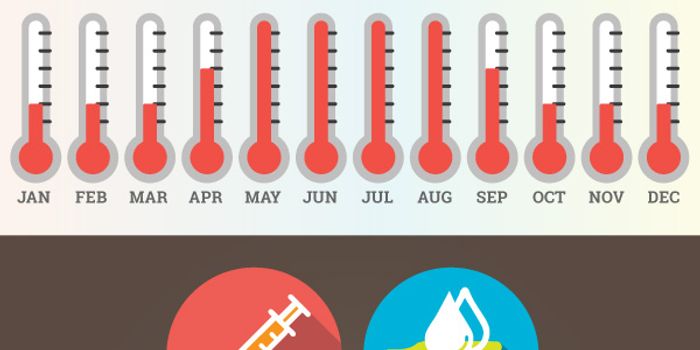

JAN 18, 2018VideosIt's flu season. Every year, influenza strains wreak havoc on public health. The flu can be deadly for those with immune ...